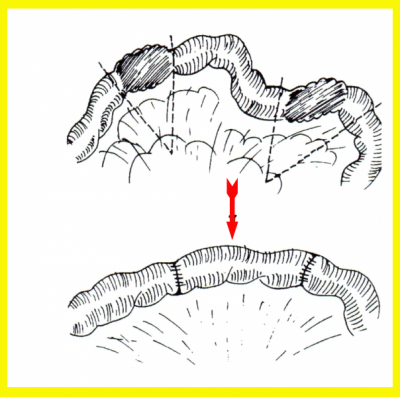

הסטריקטורופלסטיקה היא גישה "מינימליסטית" בכירורגיה של מחלת קרוהן ותוארה בתחילת שנות ה-80. בניתוח זה מבצעים חיתוך לרוחב הסטריקטורה (או לאורך המעי) ותפירת החתך לאורך הסטריקטורה (או לרוחב המעי). ניתוח זה מאפשר הרחבת האזור המוצר (איור 4.4).